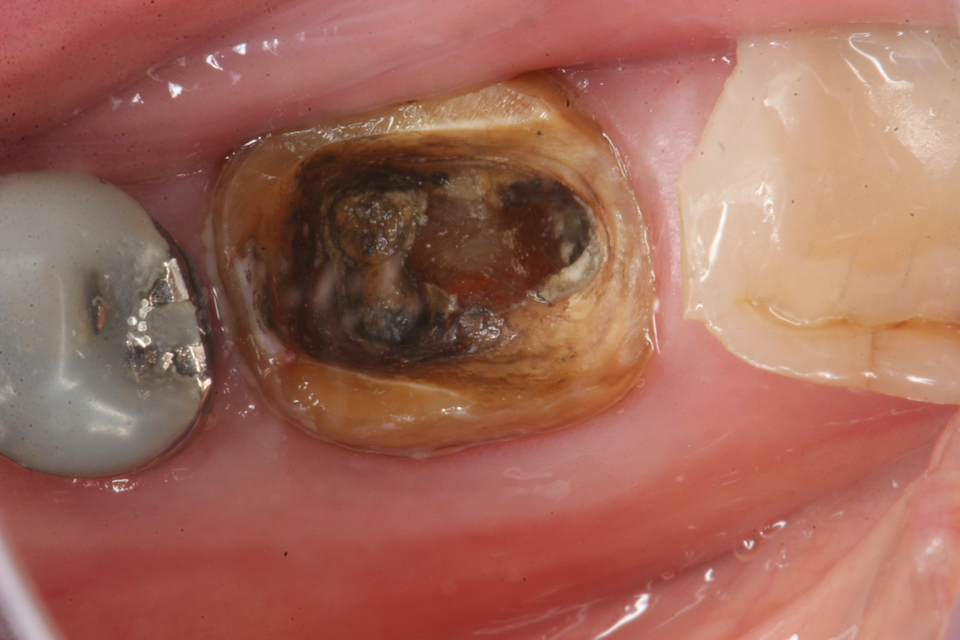

今日の抜歯再植術シリーズ39.1 2025.11.14